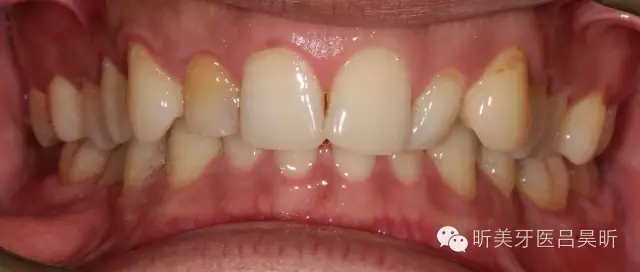

術(shù)前口內(nèi)檢查,可見牙槽骨寬度良好,角化齦量適中